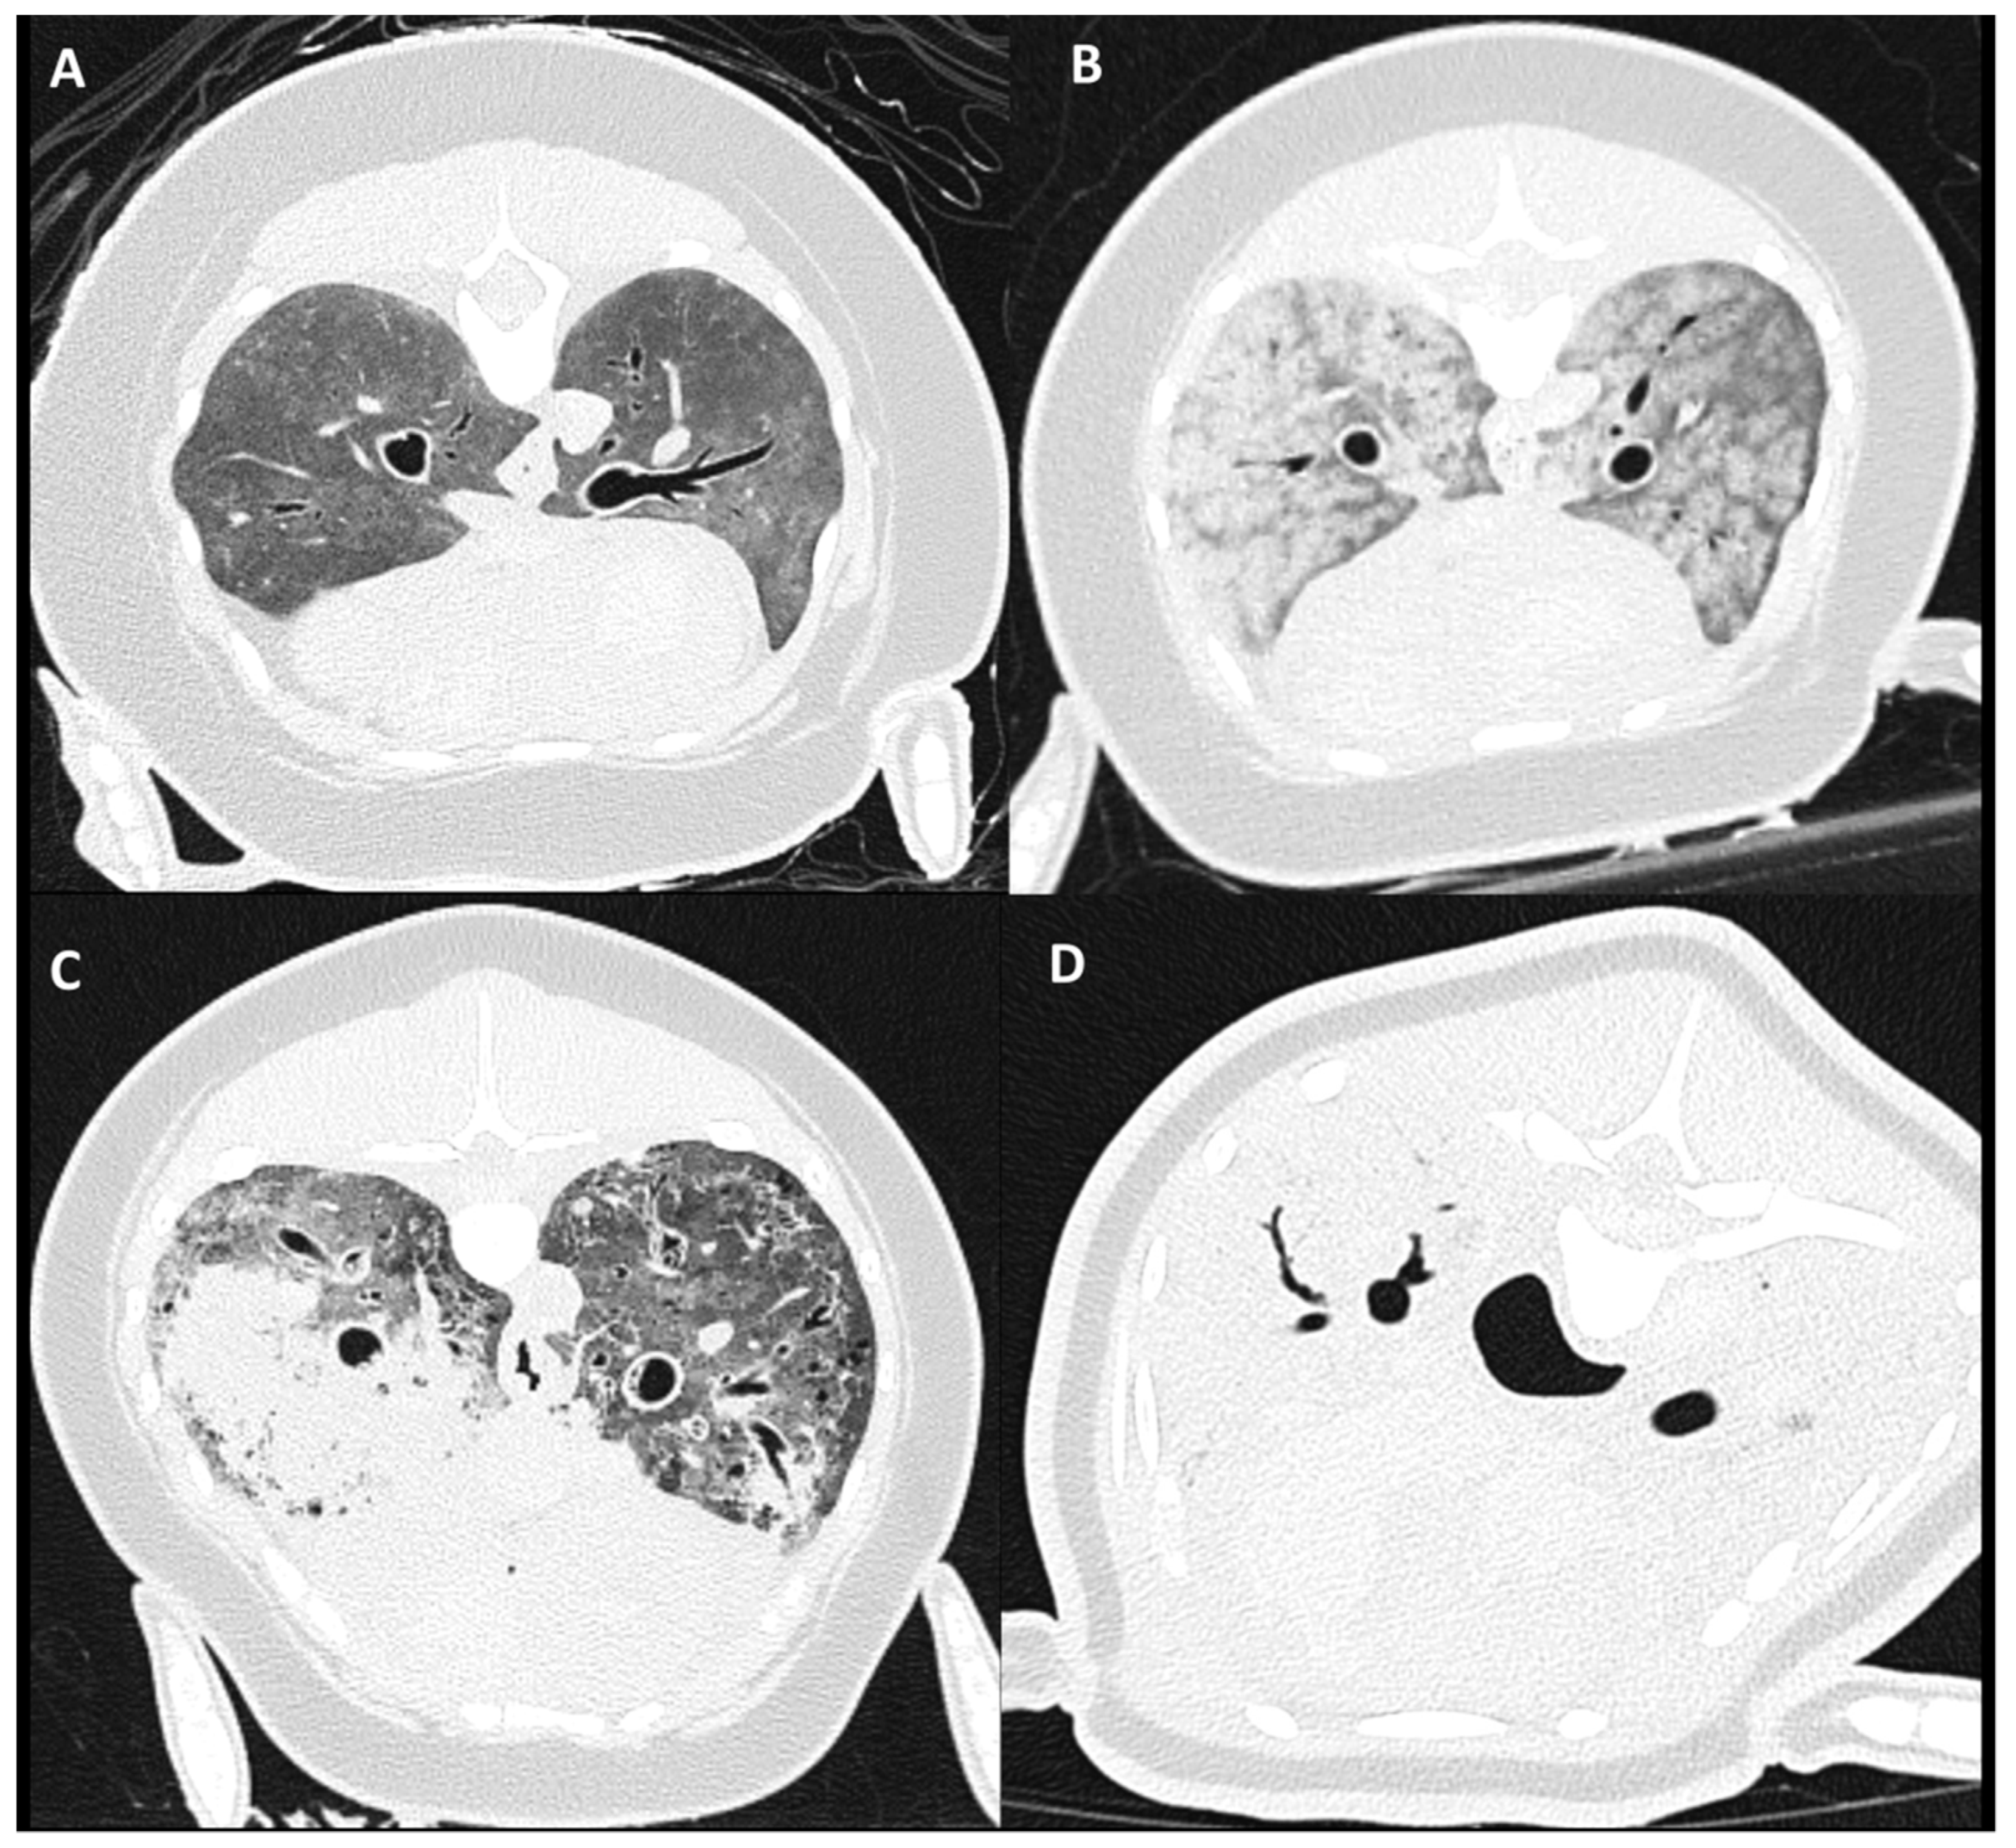

2.4. Tracheobronchial Changes

3.3. Tracheobronchial Changes